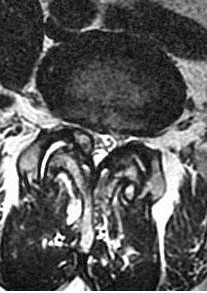

МРТ поясничного отдела позвоночника. Болезнь Бааструпа. Псевдосустав обозначен стрелками. Сагиттальная Т2-взвешенная МРТ.

Дальнейшая дегенерация суставного аппарата приводит к ослабеванию связок и их кальцификации. Костные мосты между телами 4 смежных позвонков за счёт обызвествления передней продольной связки наблюдается у 15-20% взрослых. Уменьшение высоты диска приводит к смыканию остистых отростков. В результате образуются псевдосуставы, вокруг которых развивается гранулематозное воспаление. С остеоартрозом связан также дегенеративный спондилолистез. Обычно это антелистез 4 поясничного позвонка на 5. В отличие от других этиологий может быть и не только антелистез, но и ретролистез. Степень листеза всегда небольшая.